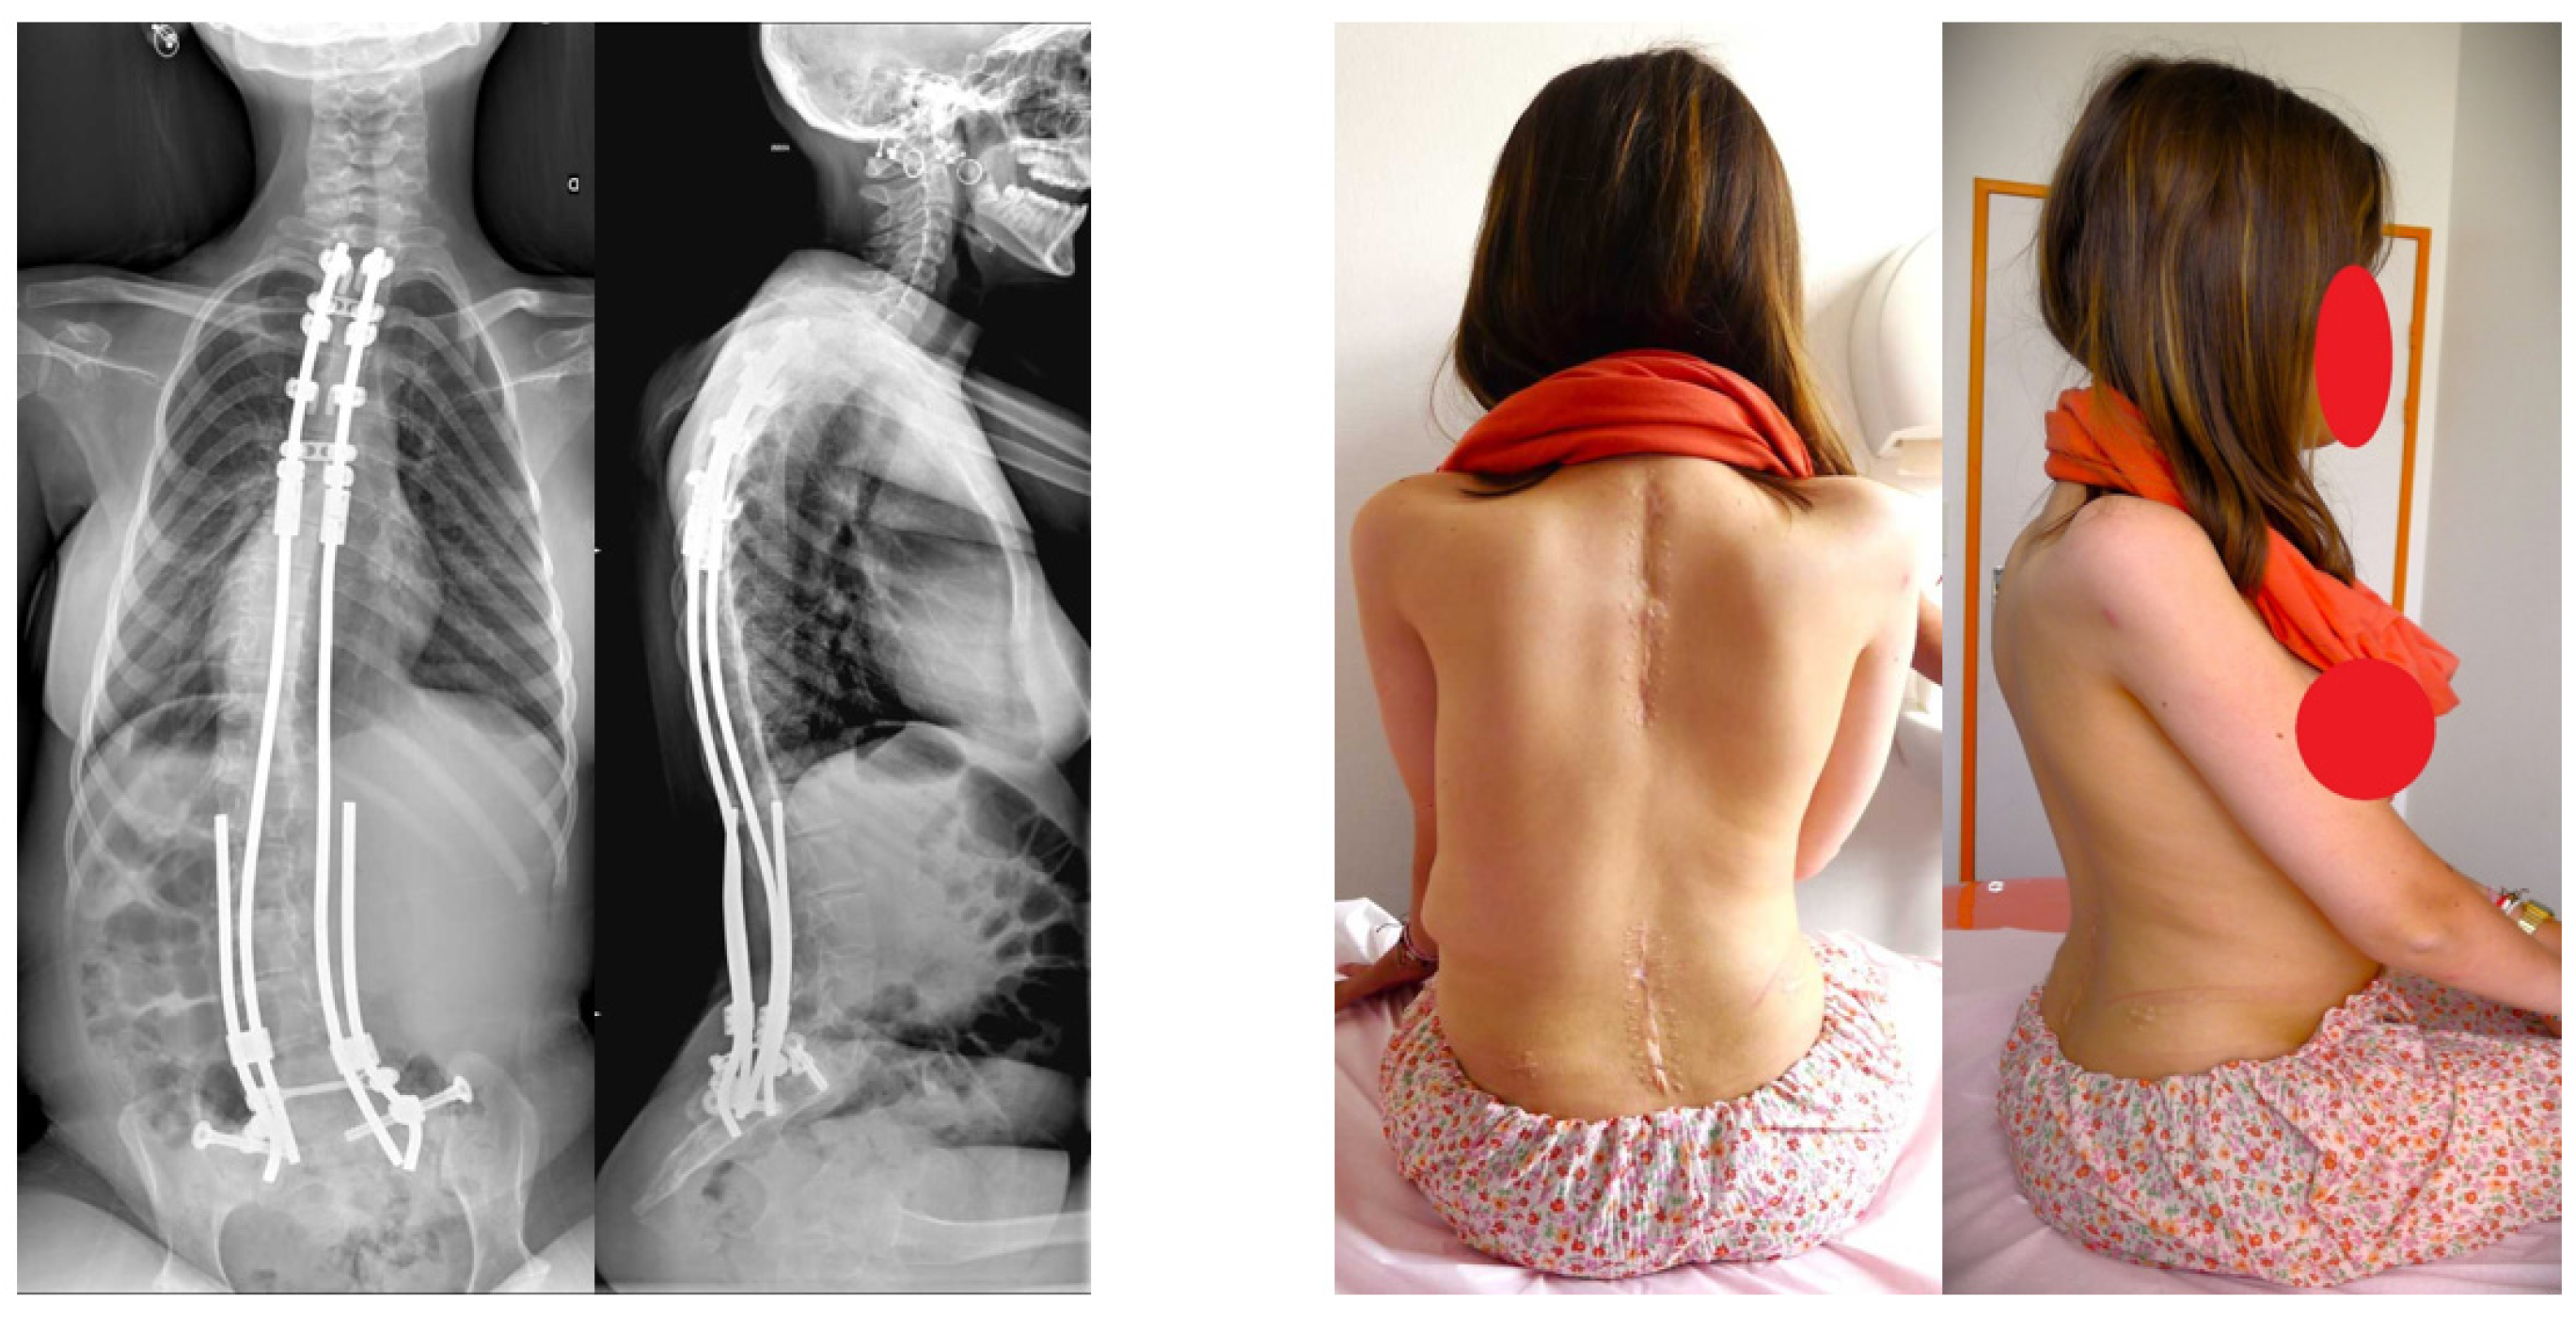

| Preoperative pelvic obliquity, (°), mean | 23 | 23 | 23 | |

| Last FU pelvic obliquity improvement (°), mean | −10.2 (44%) | −17.8 (77%) | −14 | |

| Preoperative Cobb angle, (°), mean | 50.5 | 77 | 63.8 | |

| Last FU Cobb correction improvement, (°), mean | −31.1 (61%) | −47.8 (62%) | −39.5 | |

| Loss of frontal or sagittal correction | None | None | None | |

| Sitting posture and comfort improvement | All cases | All cases | All cases |